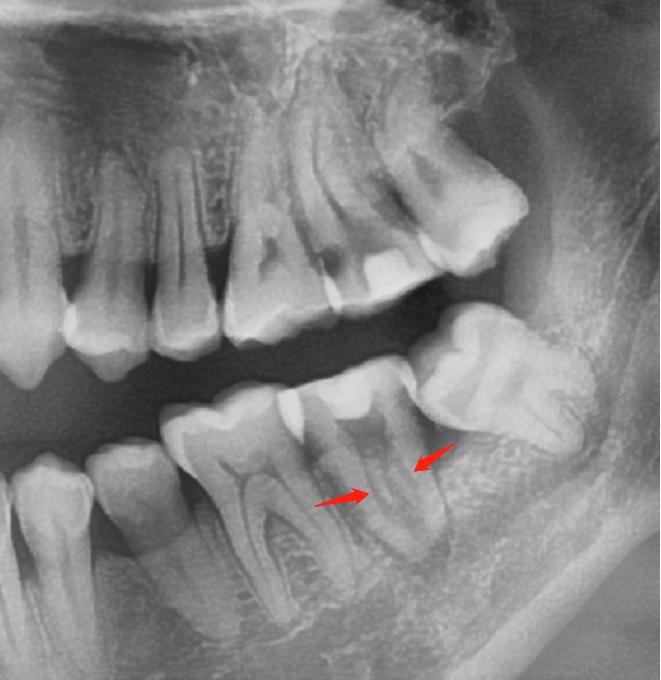

看到片子上牙根里面细细的黑色影像了没?红色箭头指的,它就是根管。根管是牙根中空的部分,里面有神经血管。